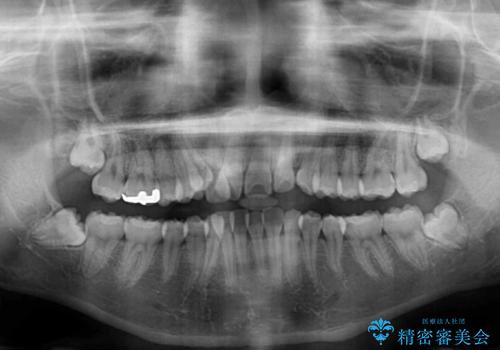

八重歯で正中が右にずれている ワイヤー装置での抜歯矯正で正中位置を改善

- 上下の八重歯と前歯のデコボコを気にして来院された患者様です。

右上の八重歯が特に著しく、上顎正中が右側にシフトしていました。

デコボコが強いため小臼歯4本を抜歯し、上顎正中を左側に移動させるために補助装置を使用して、ワイヤー装置にて矯正治療を行うこととしました。